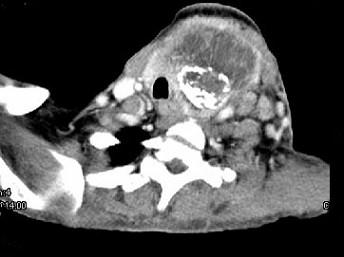

问题 女,64岁,发现双甲状腺肿大一月余,CT如图所示,最可能诊断为 ( )

选项 A、甲状腺转移瘤 B、甲状腺结核 C、甲状腺腺瘤 D、甲状腺癌并淋巴结转移 E、结节性甲状腺肿

答案 D